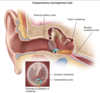

diagnostic criteria for Acute Otitis Media -2

________________

Which organisms cause AOM? -3

BULGING TM + [Middle Ear effusion with TM inflammation (fever/otalgia/erythema)]

________________

STREP PNEUMO = [HFLU NONTYPEABLE**] >> moraxella

________________

** also causes otitis conjunctivitis syndrome

Prophylactic abx tx and tympanostomy tube ⬇︎ [recurrent AOM],

and are recommended for which 4 patient groups?

[≥ 3 AOM in 6 mo] or

[≥4 AOM in 12 mo] or

[craniofacial DO] or

[neurodevelopmental DO = speech/hearing ❌]